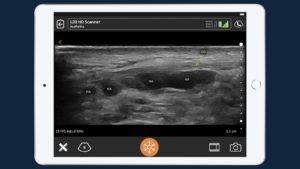

A double board certified facial plastic surgeon, Dr. Stella is known to use ultrasound at her practice to look for vessels before filler injections, improving both patient safety and confidence.

This Video Shows Normal Blood Flow During the Patient’s Ultrasound Exam the Next Day

Prior to acquiring the Clarius L20 HD in 2020, Dr. Stella hadn’t used ultrasound since her time in residency. She is mostly self-taught through online learning, reading books, and hands-on practice.

The miniaturization of high-definition ultrasound and advances in artificial intelligence has made it easy and affordable to add Clarius HD to your aesthetics practice. Dr. Weiner and Dr. Stella are using the Clarius L20 HD: ideal for facial aesthetics, it’s the world’s first ultra-high-frequency handheld ultrasound scanner designed for superficial scanning. Contact us today or request an ultrasound demo to see the difference ultra-high-definition imaging makes in facial vascular mapping.